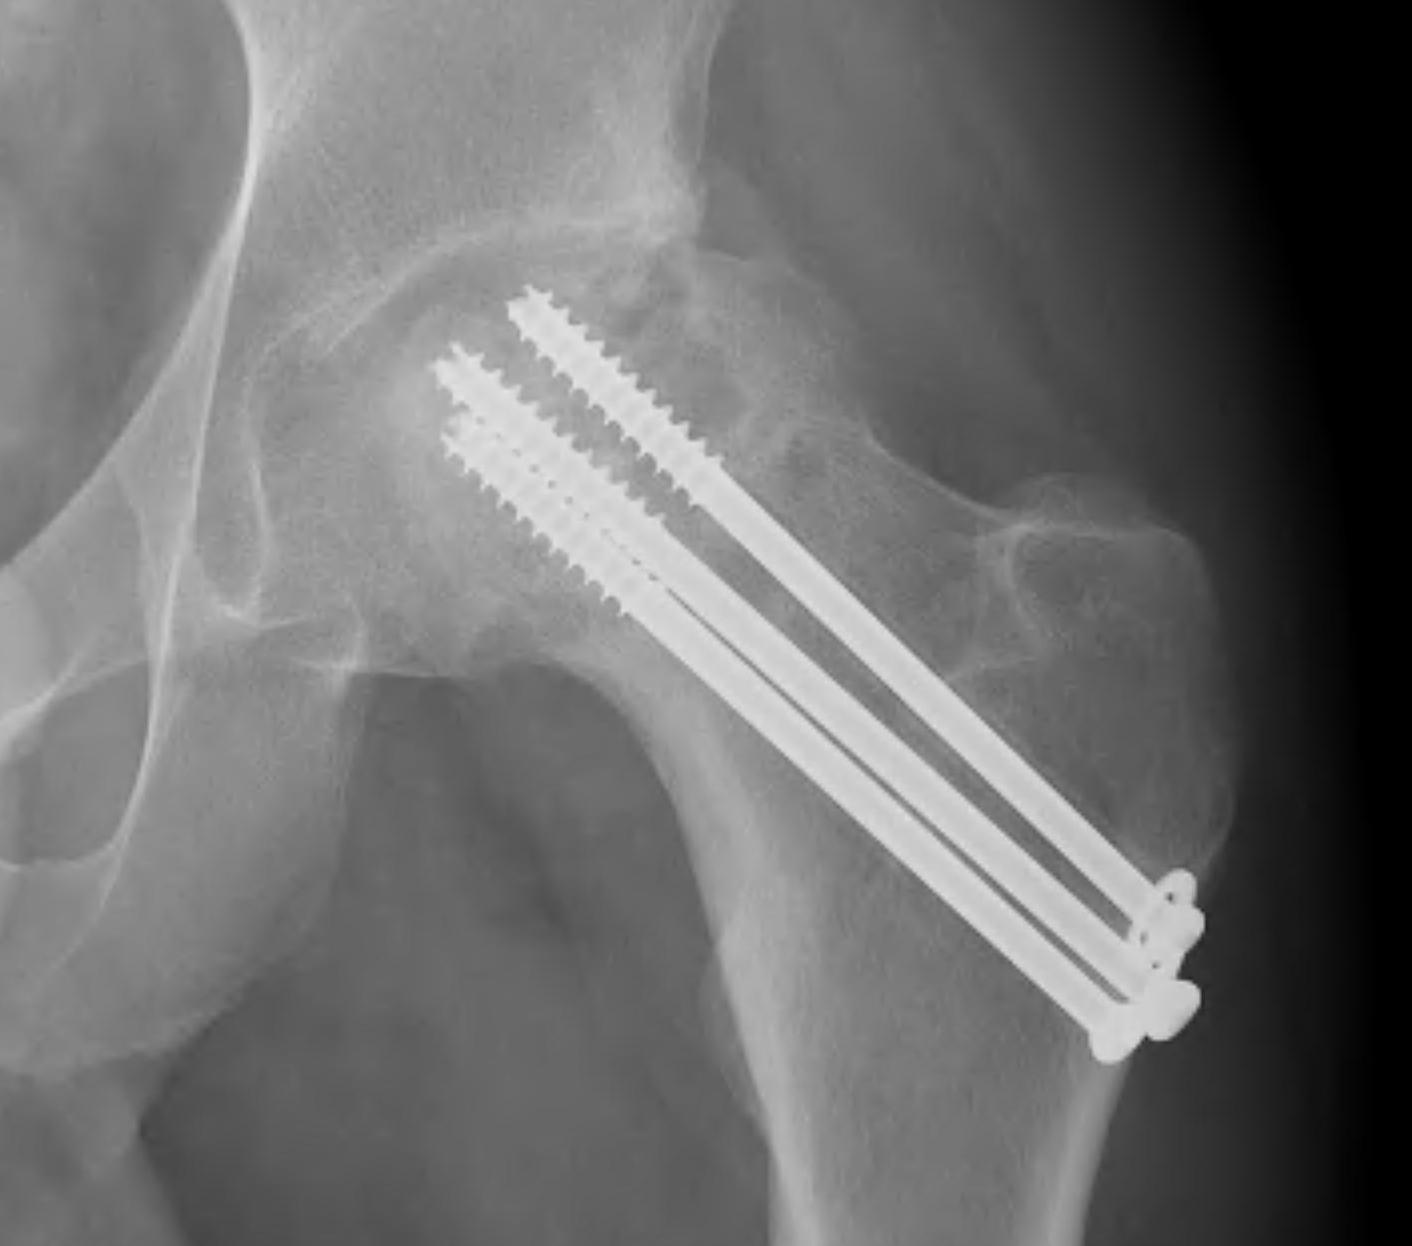

Cannulated screws

Technique

Lateral on traction table

- adequate reduction / no varus

- small incision or percutaneous

- 3 screws

- ensure inferior screw entry point is above lesser trochanter to prevent fracture

- ensure threads cross fracture site entirely to obtain compression

- need correct screw length so screw head can compress against cortex